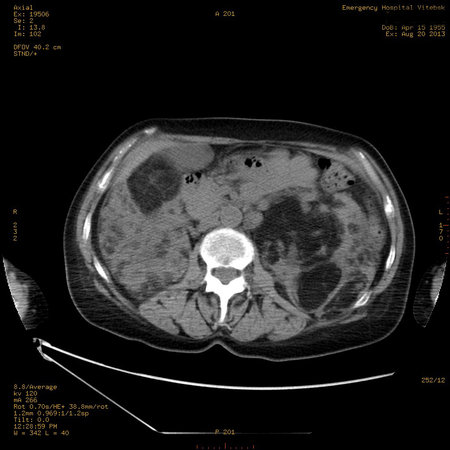

Пожилая женщина с нормальными мочевиной и креатинином.

Ангиомиолипоматоз почек , думаю компонент туберозного склероза.

Да, туберозный склероз.

Случай консультирован на кафедре радиологии Католического университета г.Лёвен (Бельгия) - зав каф. профессор Р.Оуен.